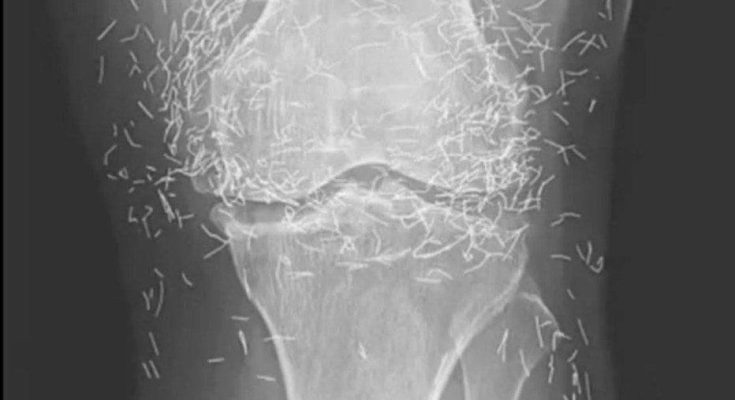

When a 65-year-old woman in South Korea went to the doctor because of worsening knee pain, no one expected the scans to reveal anything unusual. The visit was supposed to be routine — another step in managing the osteoarthritis that had slowly been reshaping her daily life.

Instead, doctors found something that stopped them cold.

For years, she had lived with osteoarthritis, a condition that quietly erodes the cartilage meant to cushion the joints. At first, it was stiffness in the morning. Then swelling. Then pain that lingered long after she sat down to rest. Simple things — climbing stairs, standing up from a chair, walking more than a few minutes — became exhausting calculations of how much discomfort she could tolerate.